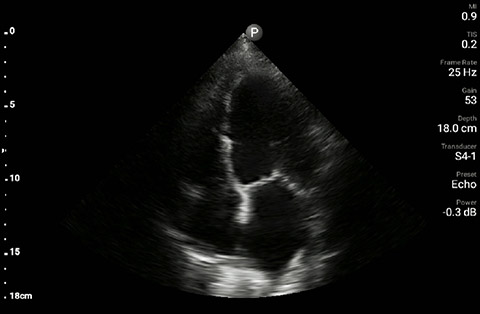

The patient had reduced LV systolic function without new or severe valvular pathology, a dilated, non-collapsing IVC, and diffuse B lines (left greater than right) on lung ultrasound imaging.

Apical 4-chamber

In the interim, while awaiting laboratory results and chest X-ray imaging, POCUS with a three-point exam (F-TTE, IVC collapsibility, and lung ultrasound) was used for bedside evaluation of the etiology of the patient’s dyspnea. Within minutes, and with the additive information from the combined cardiac, subcostal IVC, and lung ultrasound imaging, the patient was diagnosed with acute on chronic congestive heart failure and flash pulmonary edema as the cause of his respiratory distress and hypoxia.